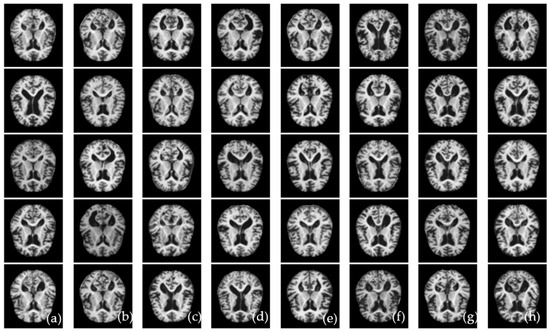

Whereas the Talo-ResNet-50 [21] used a transfer-learning-based architecture such as ResNet-50 to classify AD disease, the Gunawardena-CNN-SVM [23] used CNN and SVM classifiers to detect AD disease. Wang-CNN-Maxpool [26] used classification based on an eight-layer CNN model with leaky rectified linear units and maximum pooling. These studies were selected because they are easily implemented and can be compared with the proposed deep-learning architecture based on ConvMixer and the RF classifier. The corresponding results in terms of confusion matrices are shown in Figure 8. Compared to other approaches, the Talo-ResNet-50 [21] shows a higher classification result for AD in two stages (demented and non-demented) and four stages (very mild, moderate, mild, and non-demented). In addition, Figure 8f shows another study that outperformed the first, which was based on the Gunawardena-CNN-SVM [23] system to detect AD disease in terms of two stages and four stages. Accordingly, those results demonstrate that the proposed technique produced better classification results than state-of-the-art approaches.

Figure 8.

An example of confusion matrix for state-of-the-art systems to recognize four stages of AD such as non-demented, mild dementia, moderate dementia, and very mild dementia. Where (a) shows Murugan-DEMNET-CNN [15], (b) represents Mehmood-Siamese-CNN [16], (c) presents Islam-Deep-CNN [17], (d) shows Janghel-VGG16-SVM [19], (e) represents Talo-ResNet-50 [21], (f) shows Gunawardena-CNN-SVM [23], and (g) shows Wang-CNN-Maxpool [26] systems.

Overall accuracy success was achieved in the classification process, with 99.69% accuracy. There were 39 s that passed during the categorization procedure. Figure 7 displays the fifth step’s confusion matrices. Furthermore, Figure 8 provides the analysis findings from the cross-validation procedure. In this confusion matrix, the accuracy success demonstrated the effectiveness of the suggested strategy. The cross-validation procedure has proven the proposed approach’s stability. In Figure 8, a comparison between the proposed ALZ-CAD framework and other relevant cutting-edge studies is made. There is little doubt that the ALZ-CAD framework performs better than most of the related research. Designing a broad framework that makes use of the ConvMixer layer and a blockwise fine-tuning strategy to extract deep features is one of the key goals of the recommended methodology. The recommended framework’s insensitivity to datasets and their outliers, as explained in Section 3.4, is one of its key advantages.